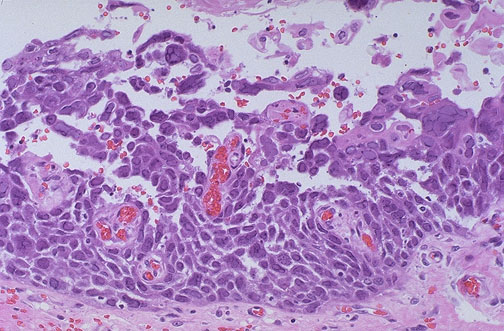

At high power magnification, multinucleated cells in esophageal mucosa from herpes simplex virus ulceration are apparent.